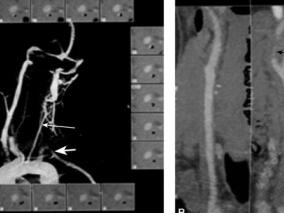

数次双眼暂时性黑矇,眼科检查与脑部CT扫描均正常,…

1小时条评论多发性大动脉炎为一影响主动脉及其分支的慢性肉芽肿性血管炎症疾病,好发于年轻女性。初期几无明显症状,然而随着疾病的进展,血管狭窄的程度会越来越严重,最后可能会导致梗死性卒中、肠系膜缺血性绞痛、肾源性高血压等。本文简短介绍一位有多发性大动脉炎的年轻女...